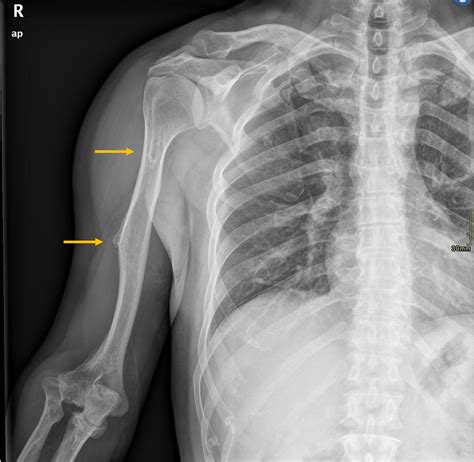

• X-Rays: Dental X-rays may be taken to assess the extent of the growth and its impact on surrounding structures.